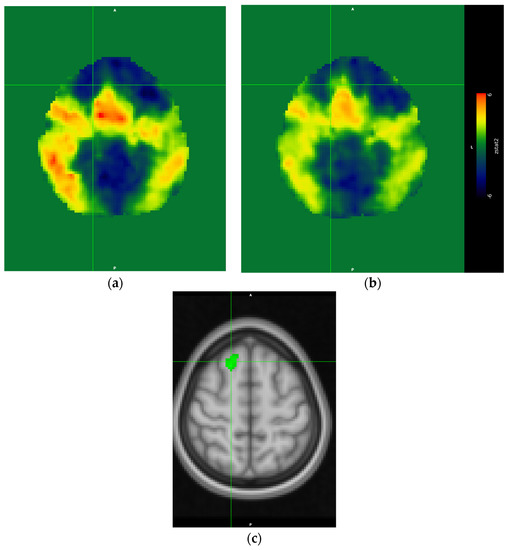

3.3.2. Contrast Results

Direct contrast between both conditions revealed a suprathreshold cluster only in the contrast fatigued > rested. The cluster was located in the right superior frontal gyrus (see Figure 4c). Interestingly, this region did not exceed the Z = 3.1 threshold in either condition, and it appeared in the fatigued > rested contrast because of the negative Z values in the rested condition (see Figure 4a showing the unthresholded Z values) and positive Z values in the fatigued condition (Figure 4b shows the unthresholded Z values). Thus, the difference of activation of this region in both conditions was caused by low response of this region in the rested condition and the moderately elevated response in the fatigued condition.

Figure 4. Unthresholded Z-statistics image of rested condition results (a), unthresholded Z-statistics image of the fatigued condition results (b). Note the larger extension of activations in the rested condition (a) as compared to the fatigued condition (b). The region of statistically significant differences; i.e., the contrast fatigued > rested conditions thresholded at Z > 3.1 (c). The crosshairs indicate the same voxel at the center of the suprathreshold cluster in the right superior frontal gyrus (MNI coordinates: x = 18, y = 26, y = 56, cluster volume = 136, Z-score (maximum—4.53)).

However, at the same time we observed a notable decrease of the extent of activation in the fatigued condition, indicating a less-consistent brain response to the experimental task across participants. Interestingly, we observed a more lateralized pattern of activation in the fatigued condition, with the majority of clusters located within the right hemisphere. We surmised that this effect might be associated with lowered brain metabolism in the state of sleep deprivation [22]. Of course, this does not mean that truck driver’s brain resembles a brain of a dolphin, yet it points to a lowered energy capacity of the fatigued brain, which can affect each hemisphere in a different manner [23]. The direct contrast between conditions revealed only one suprathreshold cluster, obtained in the fatigued > rested contrast. The reverse contrast did not reveal any significant differences. The cluster was located in the dorsal part of the prefrontal cortex. Interestingly, this region did not cross the significance threshold in any of the main effect contrasts for both the rested and fatigued conditions. However, a close inspection of the unthresholded images revealed that in the rested condition, this cluster was strongly deactivated, and in the fatigued condition, the response was positive, yet below the significance threshold. The inspection also revealed that the region discovered in the fatigued > rested contrast was a part of the larger cluster encompassing the medial frontal cortex—covering the SMA, pre-SMA, and parts of the superior frontal gyrus (see Figure 4). Previous research on the effects of cognitive working memory and attentional training research suggested that this region is a part of the cognitive control network, which is engaged in executive control over ongoing cognitive activity, and it is known that its responsiveness becomes significantly decreased over a training period [24,25]. Thus, in our case, the heightened activity of this region might suggest that a relatively simple task we used, involving simple visual feature conjunction detection, in the fatigued condition with lowered metabolic capacity due to sleep deprivation became a task that required more cognitive control resources in order to maintain the performance level. Thus, our results suggested that the influence in the arousal state of drivers on the cognitive level manifested as an increased demand for controlled attentional processing.